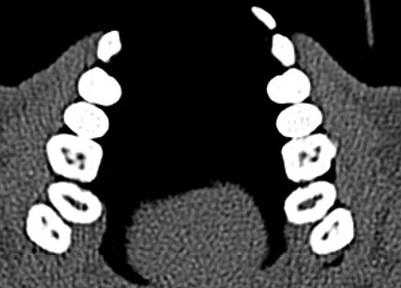

Baratto Filho исследовали внутреннюю морфологию удаленных первых моляров верхней челюсти, сравнивая с данными, полученными при осмотре в микроскоп и при получении изображений КЛКТ ex vivo. Отчеты показали наличие 4-х каналов в 67,14% зубов и дополнительные корневые каналы в 92,85 % случаев в мезиобуккальном корне. Клиническая оценка показала слегка сниженный общий показатель (53,26%), но повышенный показатель выявления MB2 (95,63%), в то время как применение КЛКТ показало 37,05%. Ученые сделали вывод, что КЛКТ является хорошим методом для начальной оценки внутренней морфологии первого верхнего моляр, но для выявления устьев самым оптимальным способом является применение микроскопа. КЛКТ также применялся для выявления высокой встречаемости дистолингвального канала у Тайванцев, выявления аномалий в системе корневых каналов нижних премоляров, и помощи в выявлении искривлении корня (Фото 2).

Фото 2: Аксиальное изображение каналов C-формы во вторых молярах